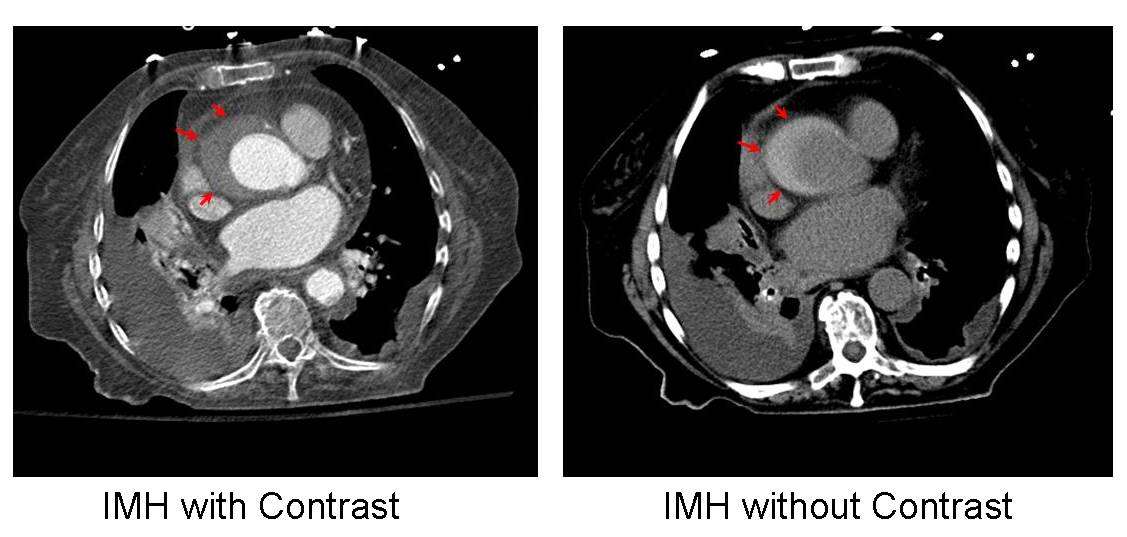

CT is the most common study to make the diagnosis. They are usually found incidentally. The CT should be performed without contrast and then with contrast. Intramural hematoma can actually be better visualized without contrast as blood is bright when the bleeding is acute. On the contrast exam, the hematoma may blend into the wall and seem like an atherosclerotic process.